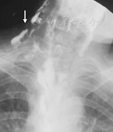

患者男,48岁。因皮肤红斑破溃伴肌无力8个月,咽痛、吞咽困难4个月于2012年2月入北京协和医院风湿免疫科。患者8个月前出现眶周、颜面、前胸、双肘关节伸侧红斑,部分破溃,伴四肢近端肌无力,上肢上举、下肢蹲起困难,伴双肩、双腕关节痛,无肿胀、晨僵;当地医院查肌酸激酶(CK)升高(不详),肌电图示肌源性损害,诊为"皮肌炎",予泼尼松40 mg/d治疗后症状好转。4个月前泼尼松减量至10 mg/d,皮疹加重,出现咽痛、声嘶并逐渐加重至吞咽困难,1个月前进展至无法进食、饮水,伴发热,体温38 ℃,咳嗽、咳少量白痰,就诊于北京协和医院急诊,行喉镜检查:鼻咽、口咽后壁、声带脓苔、白膜(图1A)。留置胃管未成功,疑有食管梗阻。为进一步诊治入院。起病后体重下降20 kg。既往、个人、婚育、家族史无特殊。入院体格检查:体温36.5℃,心率90次/min,呼吸18次/min,血压95/60 mmHg(1 mmHg=0.133 kPa);营养较差,体型偏瘦,颜面、颈部、胸前V区暗红色斑丘疹,头皮脱屑。多个手指指端溃疡、坏死,左手背及左侧肘关节可见新鲜破溃,创面较深,黄色脓苔,右肩部、右肘关节、右手多个近端指间关节、掌指关节、左臀部、双足跟及第一跖趾关节伸面多处斑丘疹、溃疡、结痂。咽后壁深大溃疡,附黄白色脓苔。颈部、右胸部皮下握雪感。双下肺闻及少量湿啰音。心、腹(–)。双下肢无水肿。双上肢近端肌力Ⅳ级,双下肢近端肌力Ⅴ–级。实验室检查:血常规:白细胞5.45×109/L,血红蛋白111 g/L,血小板143×109/L。血生化:丙氨酸转移酶59 U/L,天冬氨酸转移酶34 U/L,白蛋白22 g/L,肌酐62 μmol/L,尿素12.25 mmol/L;CK 13 U/L,乳酸脱氢酶293 U/L。超敏C反应蛋白(hsCRP)21.49 mg/L;红细胞沉降率(ESR) 77 mm/1 h;免疫球蛋白、补体、类风湿因子正常;抗核抗体、抗可提取核抗原抗体、抗磷脂抗体、肌炎抗体谱阴性。肿瘤筛查:CA125稍高,余正常。全身骨扫描、腹部CT正常。胸部CT(图2A):双肺间质病变,左肺尖肺大泡,胸膜增厚,右侧胸部皮下、纵隔气肿。心脏超声:左室顺应性减低,微量心包积液。咽部溃疡活检病理:急慢性炎,可见炎性渗出坏死及真菌菌丝。六胺银染色(+)。上消化道造影:喉咽部瘘,皮下、纵隔显影(图3),食管下段可疑狭窄。皮肤破溃处拭子培养:甲氧西林敏感金黄色葡萄球菌。

诊断皮肌炎,肺间质病变,咽部穿孔,咽喉真菌感染,皮下、纵隔气肿。予甲泼尼龙40 mg/d静脉输液治疗,静脉注射环磷酰胺(CTX)0.4 g/周治疗,同时两性霉素B、先锋美他醇等抗感染治疗。CT引导下置入空肠营养管行肠内营养支持,局部皮肤破溃伤口每日换药。经近3个月的治疗,患者体温正常,颈部、右前胸皮下握雪感消失,咽部、声带溃疡融合、变浅(图1B),声带运动恢复,皮肤红斑、破溃变浅,四肢肌力好转,复查ESR、hsCRP降至大致正常,胸部CT肺间质病变好转,皮下、纵隔气肿消失(图2B),一般情况改善,拔除空肠营养管,恢复自主饮食,激素改为泼尼松50 mg/d口服出院。出院后激素规律减量,继续使用CTX静脉注射0.4~0.6/2周,目前随诊1年余,病情稳定,泼尼松已减至5 mg/d,CTX 50 mg隔日1次口服,皮肤破溃已痊愈,肌力恢复正常。

患者有咳嗽、咳痰及皮下积气,胸部影像学示肺间质病变、纵隔气肿。皮肌炎的肺间质病变发生率高,尤其在无(或轻)肌病的皮肌炎患者,肺间质病变病情重,进展快,严重影响患者生存率。纵隔气肿是皮肌炎较罕见的并发症,好发于有肺间质病变的皮肌炎患者[4],发生率0.9%[5]~8.3%[6],气体可由纵隔蔓延至皮下组织形成皮下气肿。纵隔气肿发病机制不明,可能与血管炎所致的气管或肺泡壁破坏有关,也可能与肺间质病变有关[7]。有研究认为,糖皮质激素治疗使组织脆弱、肺部感染破坏黏膜屏障,也是纵隔气肿发生的诱因[8]。纵隔气肿的出现常是疾病活动的提示,也是预后不良的危险因素,病死率高[5]。积极治疗原发病,尤其是环孢素等免疫抑制剂的应用[8],可显著改善患者预后。

分析该患者皮下、纵隔气肿的原因,本例肺间质病变相对较轻,而皮肌炎出现纵隔气肿一般情况下肺部间质病变严重;患者皮肤表现突出,提示血管炎程度较重,故考虑气肿的发生可能与血管炎有关。而血管炎严重是原发病活动的提示,需加强糖皮质激素和免疫抑制剂的治疗。

患者吞咽困难,虽考虑咽喉部病变为主要原因,但患者曾有留置胃管失败史,为进一步明确是否有消化道梗阻,为患者行消化道造影检查。检查中却有惊奇的发现:吞咽造影剂后,患者皮下出现造影剂显影,说明患者咽部与皮下存在贯通伤,推断原发病血管炎的损伤加之真菌较强的侵袭性,导致患者咽部穿孔,引起皮下气肿,并蔓延至纵隔形成纵隔气肿,这种情况在文献中也有报道[9]。至此,本例纵隔、皮下气肿的原因已真相大白,咽部病变损伤是真正的元凶。而咽部损伤则归咎于:(1)原发病的血管炎是始动因素,(2)继发的侵袭性真菌感染则起了推波助澜、雪上加霜的作用。